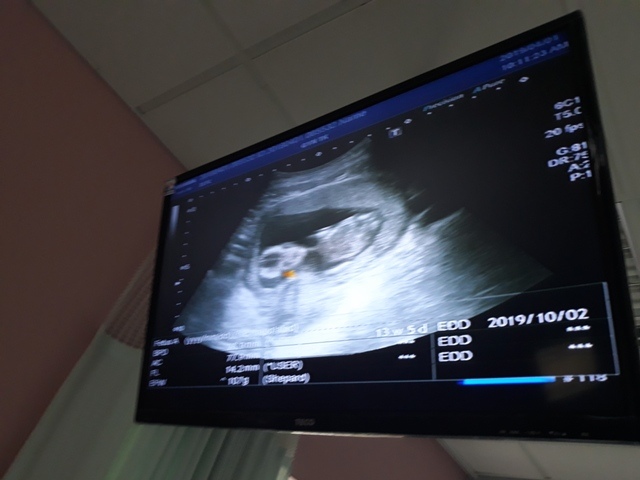

當小純進入診間看診時,我並沒有進去,因為小純說,有時男生不能進去,會被請出來。在外頭等待的我感到很緊張,不久之後,謢理人員請我進入診間,我嚇了一跳,想說發生什麼事了,進入之後,得知小純真的懷孕了,而且已懷了九星期又五天。看診的醫師說,驗孕棒第二條線淡淡的,沒想到胚胎照出來那麼大了,說Baby很健康。還說一閃一閃的是他的心跳,有頭、有手、有腳還有臍帶。小純後來說看了內心覺得很感動,才叫我一起進去看。

小純肚子裡的Baby超音波圖↓